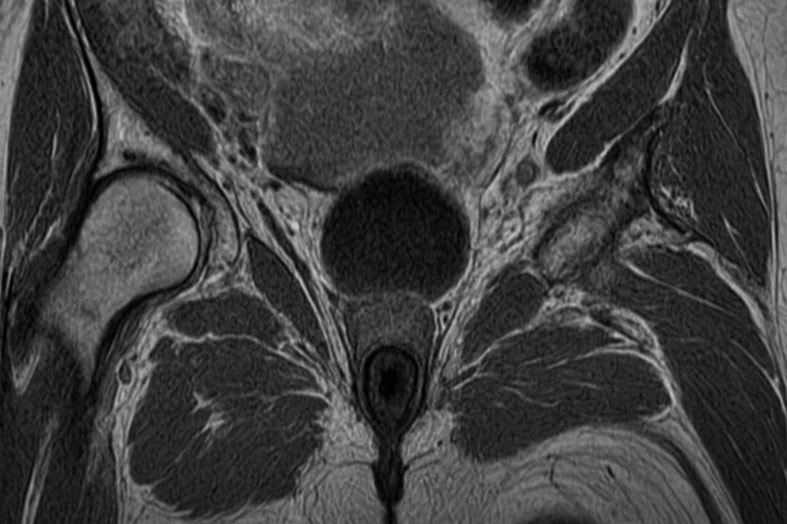

Процедура МРТ анального канала выполняется в спокойной обстановке. Пациент ложится на подвижный стол, который задвигается в тоннель томографа. Во время сканирования применяются методы визуализации, формирующие серию послойных изображений области малого таза.

При необходимости вводится контрастное вещество для уточнения сосудистого рисунка и выявления даже небольших образований. Современные методы обследования позволяют обнаружить патологии на ранней стадии, включая признаки злокачественных опухолей.

Расшифровка

После завершения процедуры врач-радиолог анализирует полученный снимок. На нем четко видны контуры тканей и структура сфинктера. Результаты МРТ позволяют определить степень воспаления, наличие кист, рубцовых изменений и новообразований.